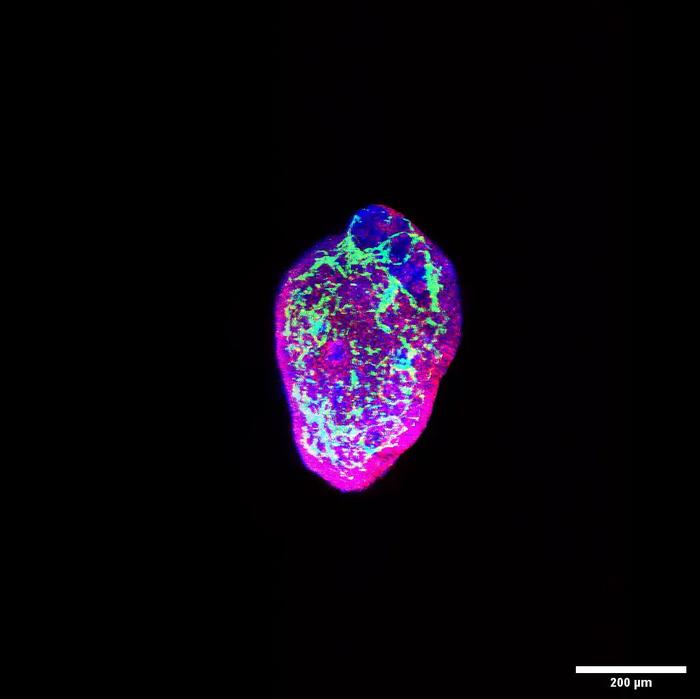

3D reconstruction of heart organoid

This video shows a 3D confocal reconstruction of an organoid surface, showing blood vessels in green and cardiomyocytes in red. Blue is cell nuclei.

Credit: Brett Volmert